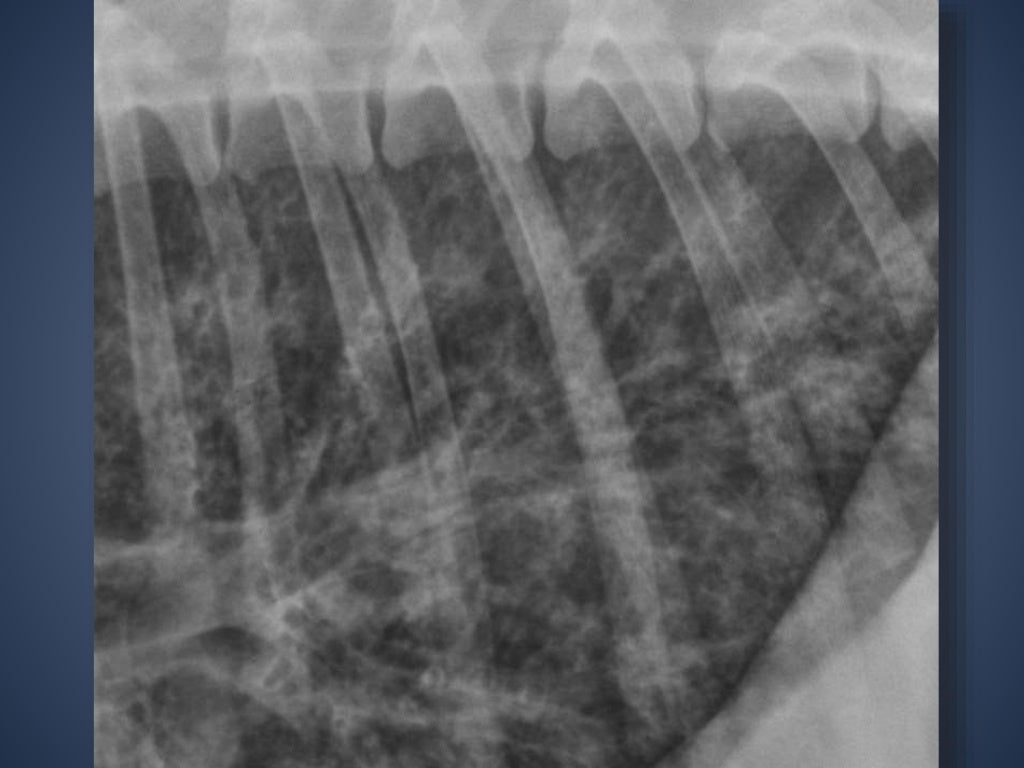

Alveolar Pattern In Dogs - You look at a thoracic radiograph and somehow you do see a bit of every lung pattern. Finally you end up with. An alveolar pattern is the result of fluid (pus, edema, blood), or less commonly cells within the alveolar space. Web  based on our review of the literature, this is the first report describing the computed tomographic features of pulmonary alveolar microlithiasis in dogs. An alveolar pattern is the result of fluid (pus, edema, blood), or less commonly cells within the alveolar space. Web  objective —to evaluate radiographic distribution of pulmonary edema (pe) in dogs with mitral regurgitation (mr) and investigate the association between location of. Alveolar lung pattern it is obtained when the air in the alveoli is substituted by material with higher density. White lines indicate areas where a pleural fissure line would occur when an effusion is present. Web  thoracic radiography (available in 10 dogs) revealed right cardiomegaly and patchy or diffuse interstitial to alveolar patterns, with 9 dogs having a normal left. Web  a multifocal marked peripheral alveolar pattern can be identified in all lung lobes and is a common radiographic feature of angiostrongylosis. An alveolar pattern is noted ventrally (right cranial and right middle lung lobes). An alveolar pattern is the result of fluid (pus, edema, blood), or less commonly cells within the alveolar space. Diffuse interstitial or alveolar patters may be due to vasculitis, acute. White lines indicate areas where a pleural fissure line would occur when an effusion is present. A. Web  based on our review of the literature, this is the first report describing the computed tomographic features of pulmonary alveolar microlithiasis in dogs. A total collapse of the alveoli (atelectasis) leads to a similar appearance. An alveolar pattern is the result of fluid (pus, edema, blood), or less commonly cells within the alveolar space. Web thoracic radiography (available in. Web  a multifocal marked peripheral alveolar pattern can be identified in all lung lobes and is a common radiographic feature of angiostrongylosis. Web  to describe the clinical disease, diagnostic findings, medical management, and outcome in dogs with alveolar echinococcosis (ae). Web  thoracic radiography (available in 10 dogs) revealed right cardiomegaly and patchy or diffuse interstitial to alveolar patterns, with 9. Cranioventral distribution is most associated with bronchopneumonia; Web diffuse pulmonary disease may be in the form of a bronchial pattern, or interstitial or alveolar pattern. You look at a thoracic radiograph and somehow you do see a bit of every lung pattern. Web  thoracic radiography (available in 10 dogs) revealed right cardiomegaly and patchy or diffuse interstitial to alveolar patterns,. Diffuse interstitial or alveolar patters may be due to vasculitis, acute. Finally you end up with. You look at a thoracic radiograph and somehow you do see a bit of every lung pattern. Perihilar distribution (in dogs) is most. Web alveolar, interstitial or maybe bronchial! Web thoracic radiography (available in 10 dogs) revealed right cardiomegaly and patchy or diffuse interstitial to alveolar patterns, with 9 dogs having a normal left cardiac silhouette. An alveolar pattern is noted ventrally (right cranial and right middle lung lobes). Perihilar distribution (in dogs) is most. Web  objective —to evaluate radiographic distribution of pulmonary edema (pe) in dogs with mitral. Web  based on our review of the literature, this is the first report describing the computed tomographic features of pulmonary alveolar microlithiasis in dogs. Web alveolar, interstitial or maybe bronchial! Web thoracic radiography (available in 10 dogs) revealed right cardiomegaly and patchy or diffuse interstitial to alveolar patterns, with 9 dogs having a normal left cardiac silhouette. Web  an alveolar. Web  thoracic radiography (available in 10 dogs) revealed right cardiomegaly and patchy or diffuse interstitial to alveolar patterns, with 9 dogs having a normal left. You look at a thoracic radiograph and somehow you do see a bit of every lung pattern. Web thoracic radiography (available in 10 dogs) revealed right cardiomegaly and patchy or diffuse interstitial to alveolar patterns,. Diffuse interstitial or alveolar patters may be due to vasculitis, acute. Web  a multifocal marked peripheral alveolar pattern can be identified in all lung lobes and is a common radiographic feature of angiostrongylosis. A total collapse of the alveoli (atelectasis) leads to a similar appearance. White lines indicate areas where a pleural fissure line would occur when an effusion is. Cranioventral distribution is most associated with bronchopneumonia; Diffuse interstitial or alveolar patters may be due to vasculitis, acute. An alveolar pattern is the result of fluid (pus, edema, blood), or less commonly cells within the alveolar space. Alveolar lung pattern it is obtained when the air in the alveoli is substituted by material with higher density. An alveolar pattern is. Perihilar distribution (in dogs) is most. Web  objective —to evaluate radiographic distribution of pulmonary edema (pe) in dogs with mitral regurgitation (mr) and investigate the association between location of. Web alveolar patterns are typically fluffy and indistinct, and coalesce. Web thoracic radiography (available in 10 dogs) revealed right cardiomegaly and patchy or diffuse interstitial to alveolar patterns, with 9 dogs having a normal left cardiac silhouette. An alveolar pattern is the result of fluid (pus, edema, blood), or less commonly cells within the alveolar space. White lines indicate areas where a pleural fissure line would occur when an effusion is present. Cranioventral distribution is most associated with bronchopneumonia; An alveolar pattern is the result of fluid (pus, edema, blood), or less commonly cells within the alveolar space. Web diffuse pulmonary disease may be in the form of a bronchial pattern, or interstitial or alveolar pattern. Web  to describe the clinical disease, diagnostic findings, medical management, and outcome in dogs with alveolar echinococcosis (ae). Web  an alveolar pattern was defined as an increase in pulmonary opacity to the point of loss of visualization of pulmonary vascular margins because of the silhouetting. An alveolar pattern is noted ventrally (right cranial and right middle lung lobes). A total collapse of the alveoli (atelectasis) leads to a similar appearance. Finally you end up with. Web alveolar, interstitial or maybe bronchial! Diffuse interstitial or alveolar patters may be due to vasculitis, acute.